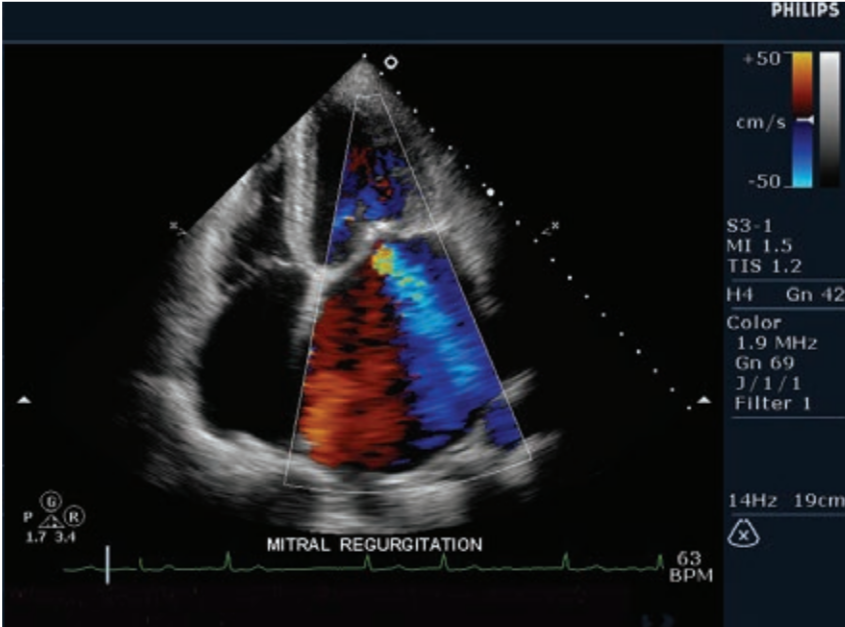

- Gracias a su software de cuantificación QLAB y sus mejoras de configuración específicas de enfermedades cardiovasculares, permite ayudarlo a realizar diagnósticos muchos más rápidos y eficientes.

- El sistema de ecocardiograma iE33 forma parte de la línea de alta gama de ecógrafos Philips.